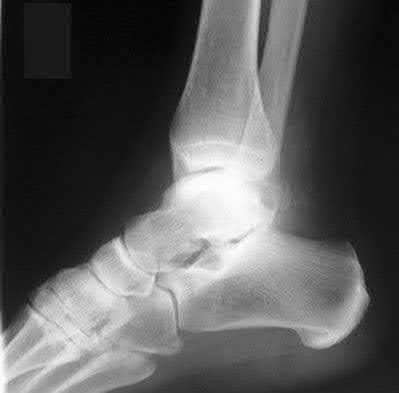

2. # A 35-year-old woman is involved in a head-on collision while driving. Initial radiographs are shown in Figures 8a and 8b. Injury to what vessel increases the risk for osteonecrosis of the injured bone?

5. Artery of the tarsal sinus Corrent answer: 4

The patient has a Hawkins type III talar neck fracture-dislocation with a risk of osteonecrosis ranging from 69% to 100%. Anatomic studies have shown that the artery of the tarsal canal supplies the lateral two thirds of the talar body.

The other vessels listed provide no significant contribution to the talus.